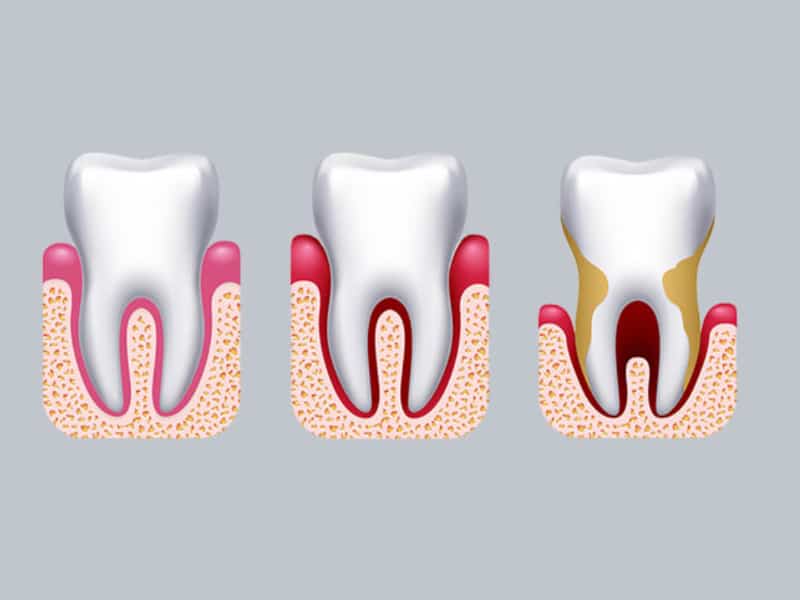

Parodontologija

Parodontologija je grana dentalne medicine koja se bavi zdravljem potpornih struktura zuba (parodonta). Parodontno zdravlje neopisivo je bitno, parodontitis je druga najučestalija bolest na svijetu i u početnoj fazi je bezbolna i nema simptoma.